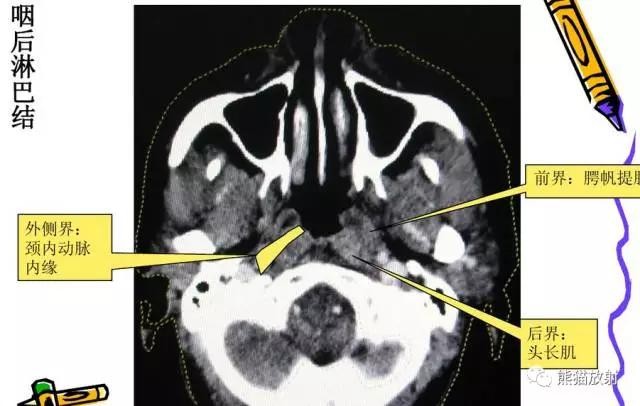

另: